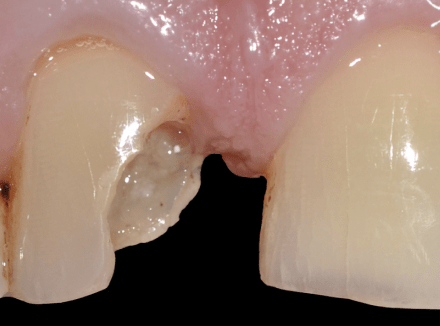

Установка керамических виниров

Пациент, возвращаясь вечером с работы, поскользнулся и упал на льду. Разбил губу с передними зубами. При травме нерв был повреждён и начал портиться, в результате чего эмаль зуба начала темнеть. Без применения виниров или коронок в такой ситуации цвет уже не восстановить. Было принято решением восстановить зубы при помощи керамических виниров.